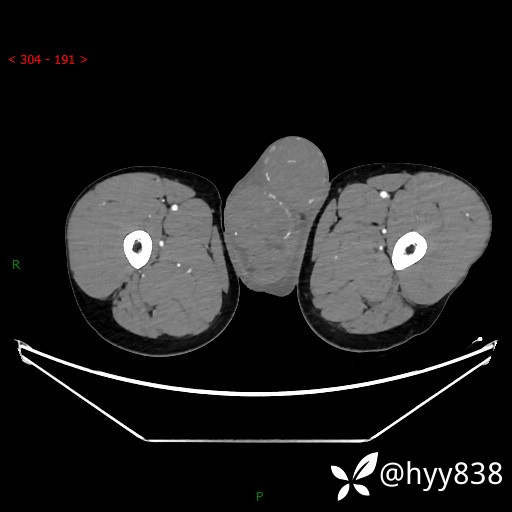

睾丸CT平扫